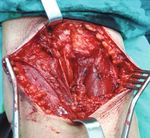

Physical examination revealed a large, palpable, and

painless soft solid mass on the upper half of the right forearm

(Figure 1). No overlying skin changes were found. Range of

A CT and MRI with contrast demonstrated a well-encap-                    Figure 1: Preoperative view of the patient’s forearm.